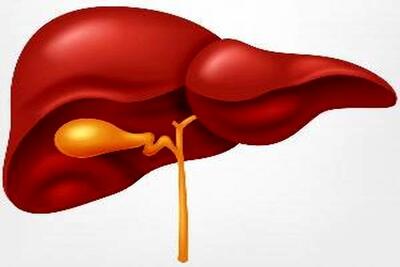

چرا بیماران سیروز کبدی به تهوع دچار میشوند؟+ علتهای پزشکی

یک فوق تخصص کبد، در خصوص اینکه چرا بیماران مبتلا به سیروز کبدی دچار تهوع و استفراغ میشوند، نکاتی را گوشزد کرد و در ادامه نیز توصیههایی ارائه داد.

علت حالت تهوع در بیماران سیروز کبدی چیست؟

یک فوق تخصص کبد، در خصوص اینکه چرا بیماران مبتلا به سیروز کبدی دچار تهوع و استفراغ میشوند، نکاتی را گوشزد کرد و در ادامه نیز توصیههایی ارائه داد.

چرا بیماران سیروز کبدی دچار تهوع می شوند - کلبه سرگرمی

یک فوق تخصص کبد، در خصوص اینکه چرا بیماران مبتلا به سیروز کبدی دچار تهوع و استفراغ میشوند، نکاتی را گوشزد کرد و در ادامه نیز توصیههایی ارائه داد.